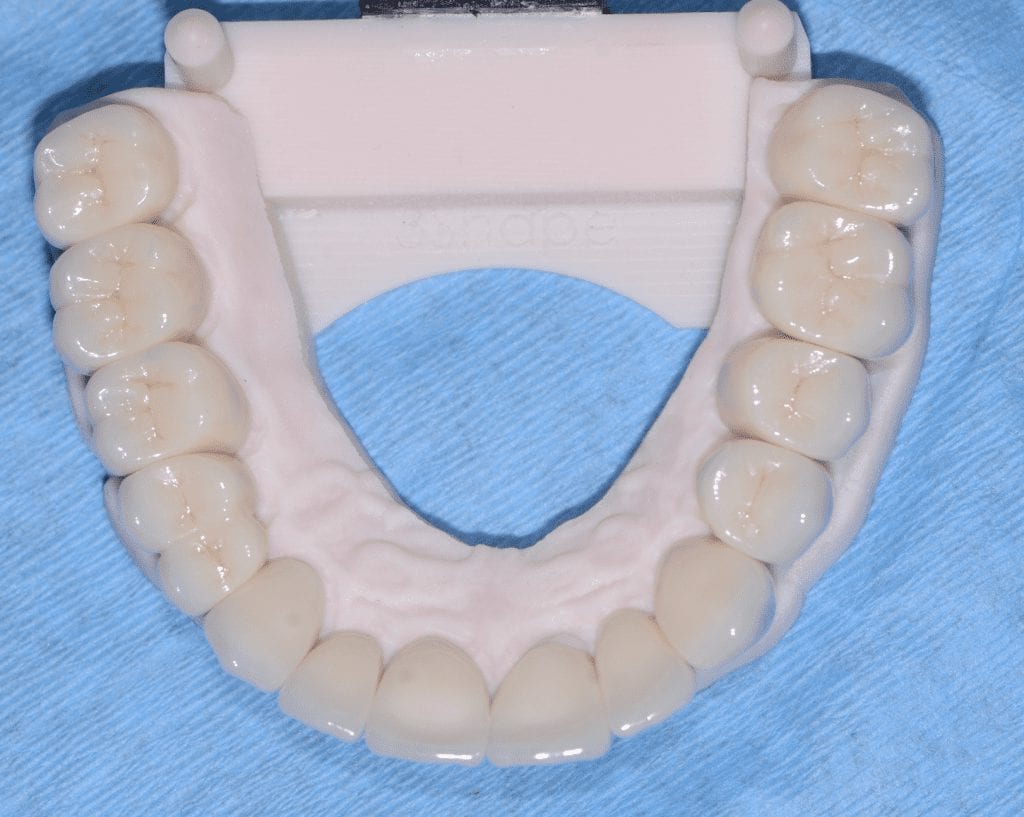

The case was designed by CADENT BESSA, and the models were printed by Burbank Dental Lab with Carbon Printers. There restorations were milled and cut back and layered by Burbank Dental Lab

IMAGES OF PRINTED MODELS